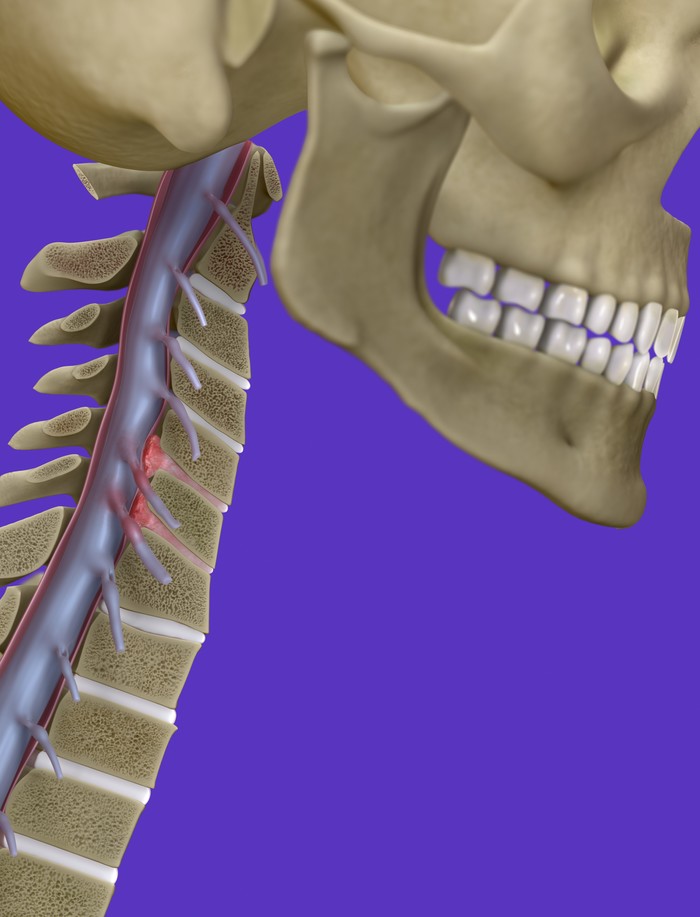

목 디스크는 목의 디스크(경추 디스크)에서 출현하는 질환으로, 경추 디스크 사이의 연골판이 터져 디스크 내부 물질이 경추 신경을 자극해 통증이나 저림증 등의 증상을 유발 해요. 목 디스크는 일상생활에서의 안 좋은 자세나 많은 운동, 부상 등이 이유가 되는 것이 될 수 있기도하고, 시간이 지날수록 발생 확률이 높아져요. 목 디스크의 증상으로는 목 부위의 통증, 팔의 저림, 근육 약화 등이 있으며, 증상이 난폭한 경우 수술 등의 치료가 필요할 수 있어요. 그리하나 대개의 경우 치료 없이도 시간이 지나면 증상이 호전되는 경우가 대부분입니다.

추간판의 수핵이 빠지거나 퇴행성 경추증 및 경추관협착증 등으로 척수가 압박되면 대다수 팔에 힘이 빠지는 것을 느끼게 돼요. 척수가 눌리는 정도이기 때문에 한쪽 팔만 마비될 수 있고요. 하지마는 양팔의 감각이 둔해지고 눈을 감고도 어지럽기 때문에 이러한 목 디스크 증상이 나타나면 무척 위험한 상태가 되기 때문에 빨리 치료가 필요해요.

척수라는 중추 신경은 목뼈를 통과해 목 아래 감각과 운동 신경에 영향을 끼치기 때문에 목 디스크 증상들이 나타나면 신속하고 빠른 대처가 필요해요. 목디스크 치료형식으로 주로 초기 스탭에는 물리치료나 약물을 통해 대개의 환자들이 호전돼요. 그렇지 않다고 하면 신경 성형술과 차단술이라고 부르는 뼈주사 목디스크 치료방법을 이용하는데, 이 치료방법은 통증이 있는 신경 부위에 약물을 삽입하는 것입니다.